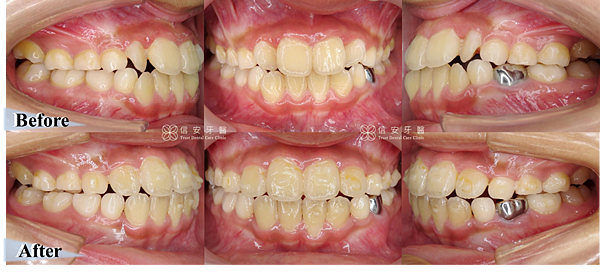

▋ 矯正前vs矯正後:

▲短短一年的時間,就把原本擁擠的齒列矯正到正確的位置上,也讓恆齒有足夠的生長空間;原本門牙上下中線不對稱,在矯正後也對齊了。

▲同時調整上下顎齒列,讓暴牙往內推。

▲透過上顎的擴張,讓擁擠的牙齒都歸隊排好,牙齒參差不齊的歪斜角度也達到一致,臉型也能一併獲得調整。

▲對比矯正前,A小弟微微一笑就能露出整齊無比的牙齒,帥度倍增!